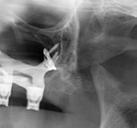

En la ortopantomografía se aprecia una dentición permanente a falta de la erupción de los 2os y 3 os molares, así como una asimetría ósea con rama y cóndilo mandibular izquierdo menos desarrollado (figura 9), causante de la asimetría facial descrita anteriormente.

Figuras 9-11.